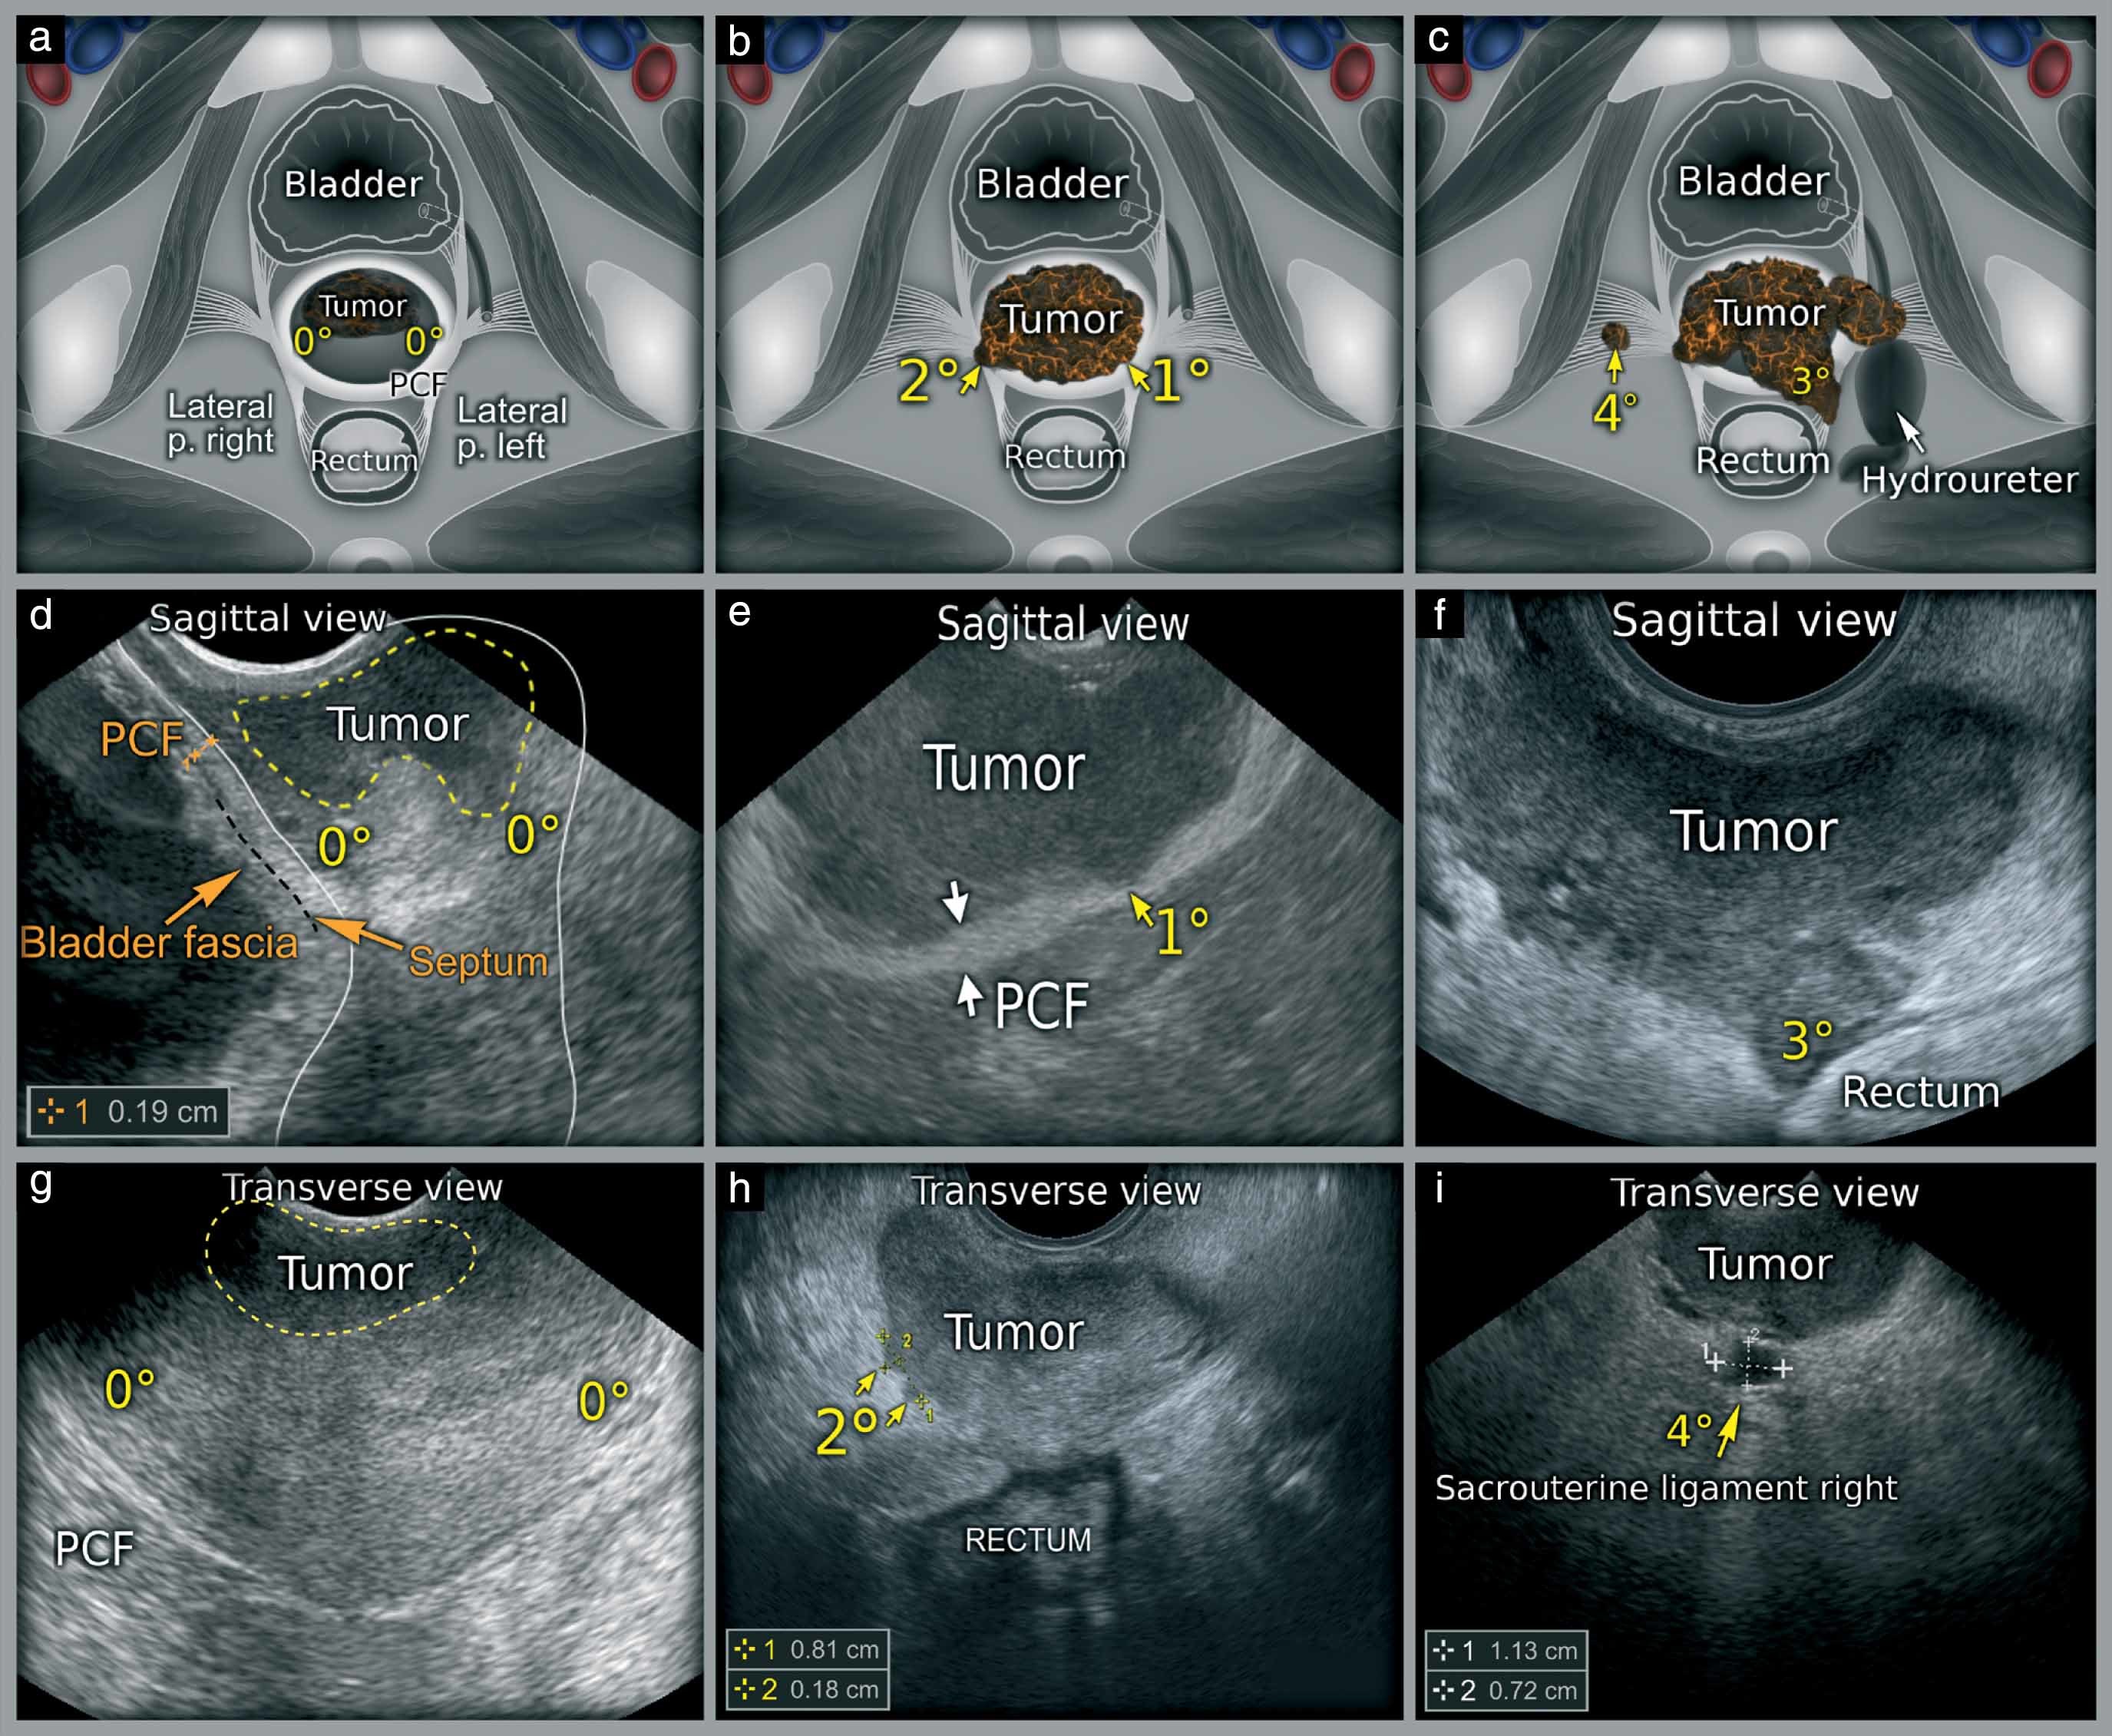

Whole abdomen and pelvic ultrasonography is a non-invasive procedure that offers invaluable insights into the body's internal structures. For Anjali, this meant having a detailed view of her abdominal and pelvic organs, providing answers to her lingering questions. The anxiety that once clouded her thoughts began to dissipate, replaced by a sense of empowerment.

This procedure is particularly beneficial for individuals like Anjali who experience undiagnosed abdominal discomfort or have a history of medical concerns that require monitoring. With its ability to identify conditions such as gallstones, liver abnormalities, kidney issues, and reproductive health concerns, it serves as a comprehensive tool for diagnosis and peace of mind.